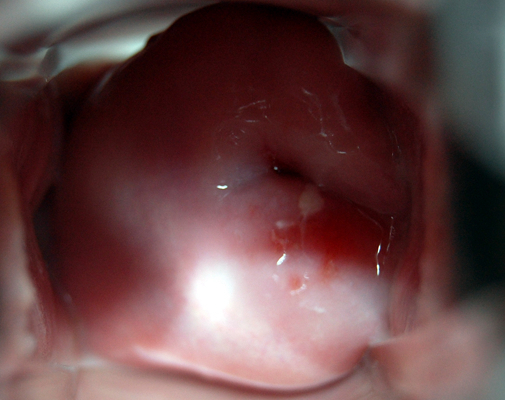

子宮肥大圖片

子宮肥大圖 (7)

子宮肥大圖 (8)

子宮肥大圖 (9)